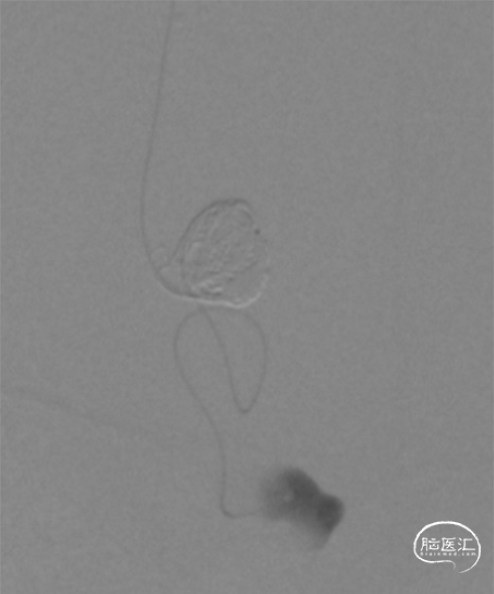

造影提示左侧前颅底眼动脉末端分支供血的DAVF经矢状窦起始段回流,回流静脉迂曲,局部可见粗大的静脉球。

斜位病灶局部造影

局部造影显示瘘口三要素:供血动脉(红色箭头),瘘口及引流静脉(静脉球),其中蓝色箭头所示静脉期正常回流静脉。

Echelon微导管经DCwire™微导丝,经过近端扭控,远端克服刁钻“回转弯”后引导微导管顺利进入近端静脉球。后马拉松微导管到达近动脉瘘口。

DCwire™微导丝配合Echelon微导管、通过优秀的扭控到位性及输送性,为微导管顺利到位提供保障。通过Echelon微导管首先稳定栓塞近端静脉球。